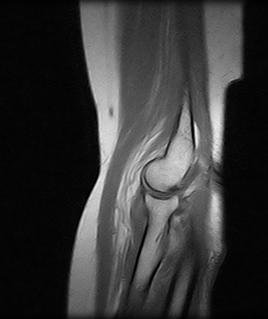

Ressonâncias Magnéticas de Cotovelo

As ressonâncias magnéticas de cotovelo visam obter informações detalhadas sobre o tecido ou órgãos do corpo, através de ondas imagens, obtendo um diagnóstico.